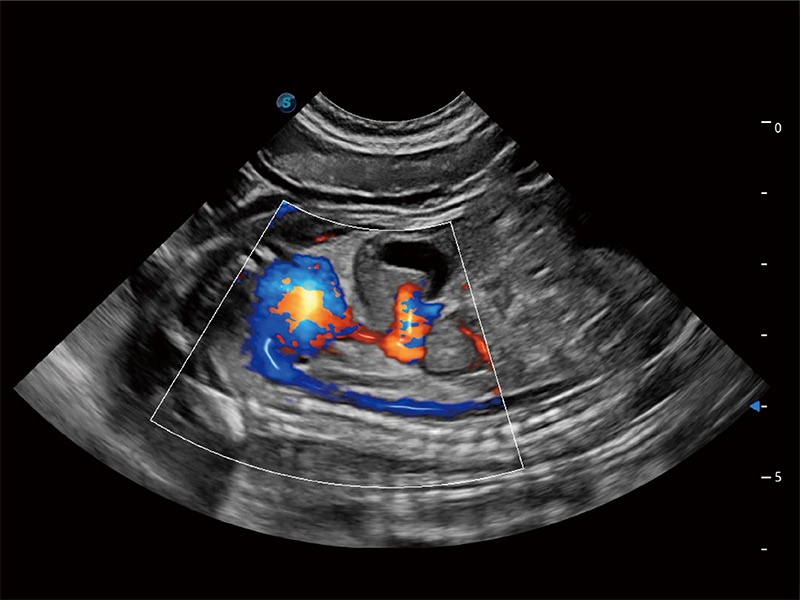

ProPet 80 配备了丰富的心脏探头群、先进的成像技术和专业的心脏测量工具,可帮助动物医生为不同体型和生理结构的动物提供心脏和心肌功能的全面评估。

实时用颜色表示心肌组织运动,观察和定量组织的运动情況,对快速检测与评估心肌的灌注和活性、电传导及心肌收缩和舒张功能等均能提供重要的诊断信息。